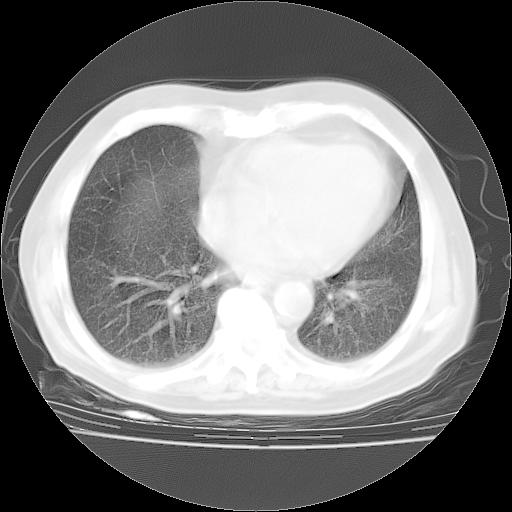

4月28日肺部CT——再次出现类似去年5月9日——透光度降低,“间质性”改变。

4月28日肺部CT——再次出现类似去年5月9日——磨玻璃样、间有“粟粒样”改变。

4月28日肺部CT